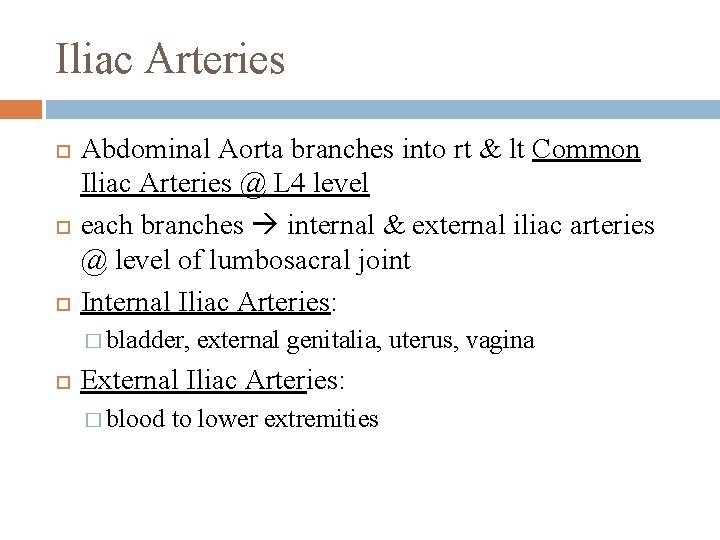

Iliac Arteries Abdominal Aorta branches into rt & lt Common Iliac Arteries @ L 4 level each branches internal & external iliac arteries @ level of lumbosacral joint Internal Iliac Arteries: � bladder, external genitalia, uterus, vagina External Iliac Arteries: � blood to lower extremities